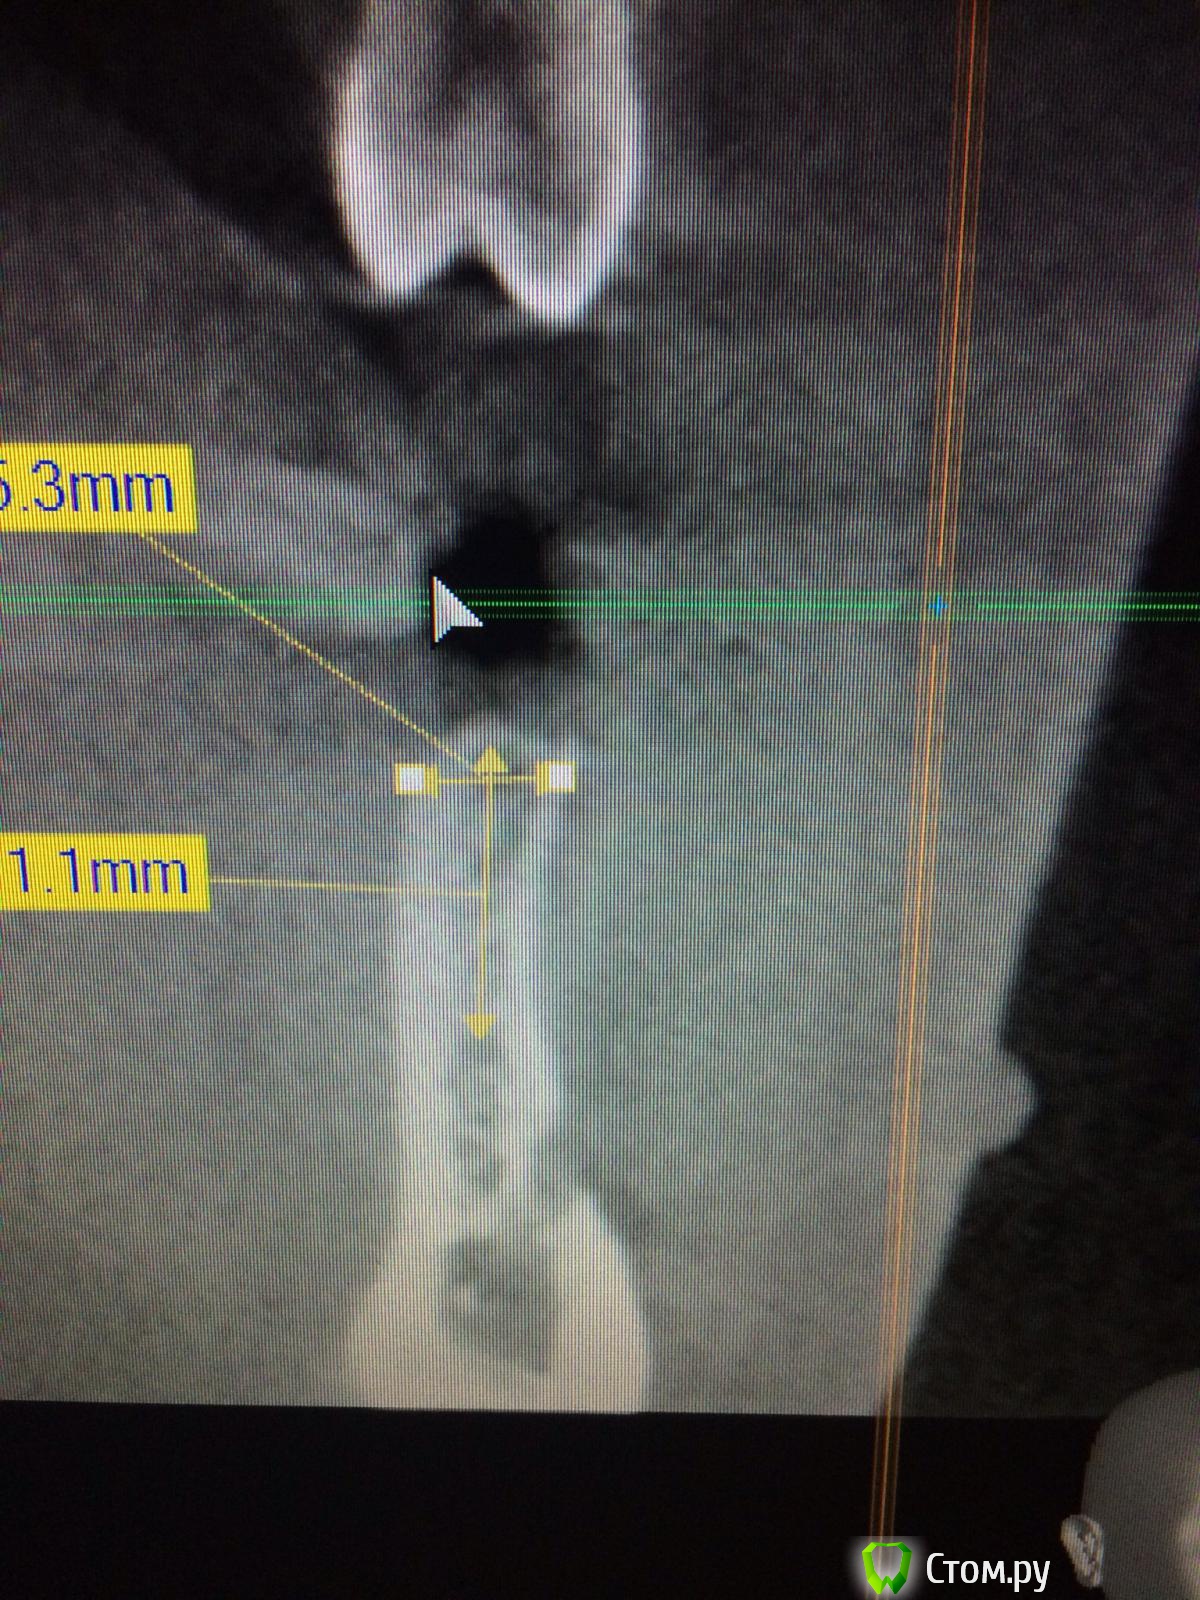

Vadim09 Опубликовано 3 октября, 2014 Поделиться Опубликовано 3 октября, 2014 (изменено) В области 3.5 отсутствует зуб, планирую поставить имплантиум 3.8, с расщеплением и подсадкой кости мис 4bone и мембраной от мис, подскажите тонкости, чтобы не сделал ошибку и простите, если вопрос не корректный. Изменено 3 октября, 2014 пользователем Vadim09 Ссылка на комментарий

doc-евгений Опубликовано 4 октября, 2014 Поделиться Опубликовано 4 октября, 2014 Имплантат 3.6 с нкр, без расщепления. Гребень с поднутрением, большая вероятность отлома. Ссылка на комментарий

faity Опубликовано 4 октября, 2014 Поделиться Опубликовано 4 октября, 2014 Расщепление не надо- может лопнуть. Ложе будете готовить пилотом пройдите, потом остеотомами работайте до нужного размера ,сверху стружки сыпануть. Ссылка на комментарий

Vadim09 Опубликовано 4 октября, 2014 Автор Поделиться Опубликовано 4 октября, 2014 (изменено) Расщепление не надо- может лопнуть. Ложе будете готовить пилотом пройдите, потом остеотомами работайте до нужного размера ,сверху стружки сыпануть.Спасибо, воспользовался вашим советом, кортикалка лопнула у шейки немног, пдсыпал биоосса и покрыл мембраной Изменено 4 октября, 2014 пользователем Vadim09 Ссылка на комментарий

k.t.m. Опубликовано 4 октября, 2014 Поделиться Опубликовано 4 октября, 2014 Спасибо, воспользовался вашим советом, кортикалка лопнула у шейки немног, пдсыпал биоосса и покрыл мембранойimage.jpgimage.jpgнадо было заглубить и более медиальнее 3 Ссылка на комментарий